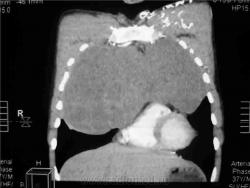

КТ август 2009.

Интенсивное, однородное затемнение в средних отделах справа, слева норма - мною был заподозрен м/долевой плеврит, пациент был направлен в областной центр торакальной хирургии. Затем онкодиспансер, затем институт рака в Киеве. Результат гистологии тератобластома средостения. 2 курса химиотерапии контрольное КТ в октябре - отрицательная динамика.